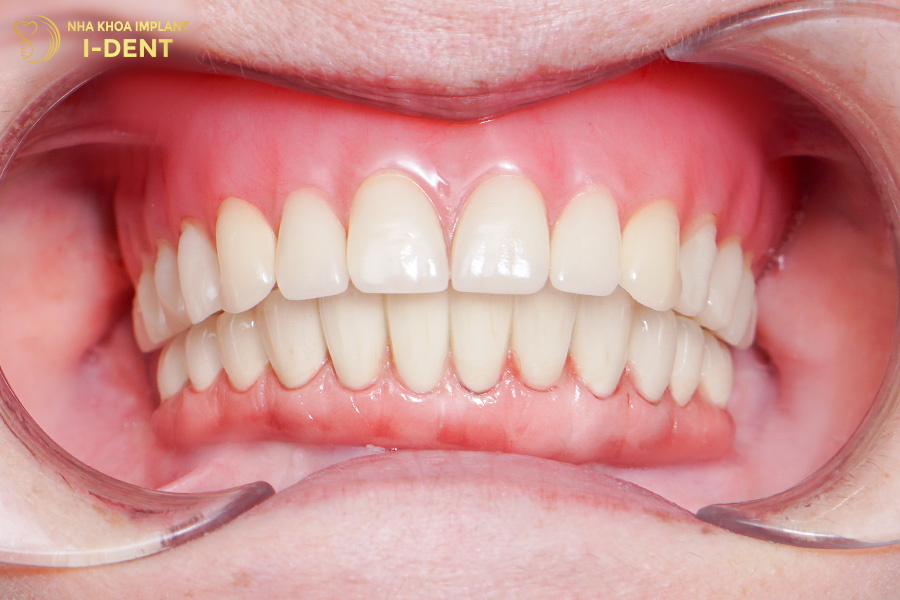

Kết thúc thời gian theo dõi và điều trị, bệnh nhân đã có thể ăn uống ngon miệng hơn trước và cũng nhờ đó mà sức khỏe cũng có bước cải tiến rõ rệt.

Hình ảnh răng chú Sự sau khi cấy ghép Implant All on 4 cho hàm trên

“Chú thấy rất là hài lòng với kết quả sau khi điều trị. Bác sĩ Tín là bác sĩ điều trị chính cho chú, chú thấy bác sĩ Tín đúng là bác sĩ có đôi bàn tay vàng. Đến hiện tại chú chưa thấy có chỗ nào để chê, từ máy móc đến tay nghề bác sĩ, cơ sở vật chất rất hiện đại, giống như một cái bệnh viện luôn vậy, rất là tuyệt vời” – Tại buổi nói chuyện, chú Sự đã dành nhiều lời khen có cánh cho bác sĩ Tín cũng như đội ngũ nha khoa I-Dent.